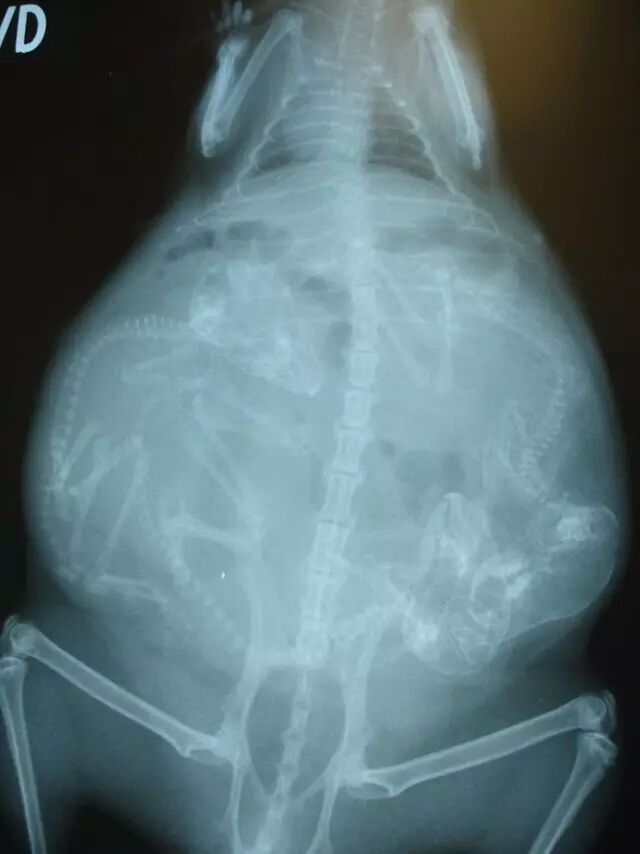

怀孕是一件神圣而又带有神秘色彩的事,她预示着新生命的来临。在动物世界,怀孕是怎样的一种奇迹,以下 14 种动物在怀孕期间的 X 线图片,我们可以通过全新的影像视角探查一番。

• 浣熊